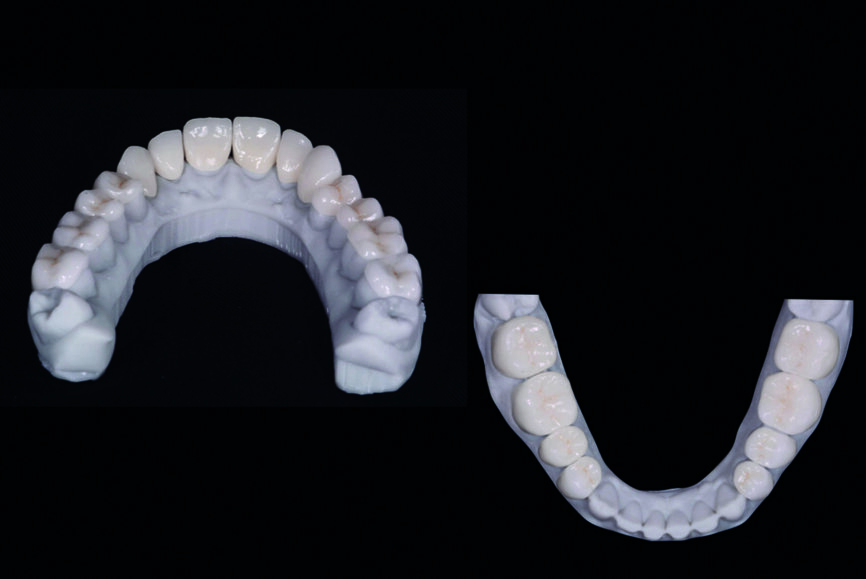

Fig. 10 : Les facettes et couronnes définitives préparées par un flux de travail numérique au moyen du logiciel de conception Ceramill Mind et fabriquées dans une unité d’usinage (Ceramill Motion 2) à partir de blocs de céramique au disilicate de lithium (VITABLOCS TriLuxe forte).

Les facettes et les couronnes définitives sont conçues numériquement par le logiciel de conception Ceramill Mind (Amann Girrbach) et produites dans une unité d’usinage (Ceramill Motion 2, Amann Girrbach) à partir de blocs de céramique au disilicate de lithium (VITABLOCS TriLuxe forte, fabriqués par VITA Zahnfabrik H. Rauter & Co. KG, et adaptés à l’usinage dans Ceramill Motion 2, Amann Girrbach; Fig. 10). Après une insertion d’essai pour confirmer la qualité du joint marginal et des propriétés optiques, un écarteur labial et jugal (OptraGate, Ivoclar Vivadent) est mis en place dans la bouche du patient.